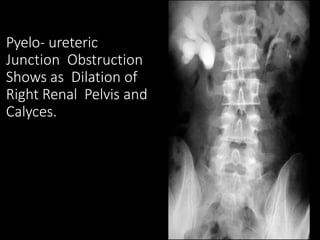

Pyelo- ureteric

Junction Obstruction

Shows as Dilation of

Right Renal Pelvis and

Calyces.